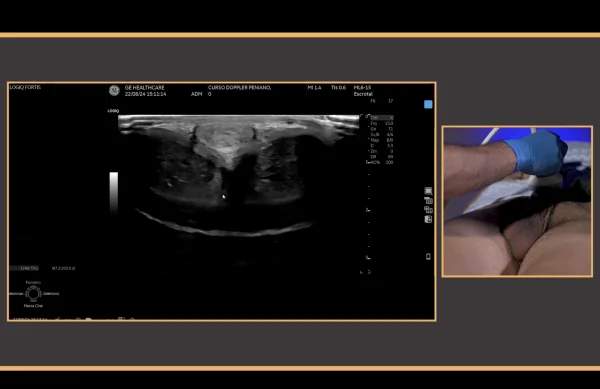

* PDU is the gold standard diagnostic modality in the vascular assessment of erectile function, and it is useful in the therapeutic decision-making process for patients with erectile dysfunction.

This video provides a step-by-step guidance in the conduction of hemodynamics studies using penile Doppler ultrasound (PDU). PDU is the gold standard diagnostic modality in the vascular assessment of erectile function, and it is useful in the therapeutic decision-making process for patients with erectile dysfunction. The video outlines the most important principles for an adequate exam conduction, which includes redosing of vasoactive agents for during erection induction, a rigidity-based assessment of hemodynamic parameters, and an effective detumescence protocol using reversal agents. The conduction of standard PDU examination of a 54 year-old man with erectile dysfunction is described.